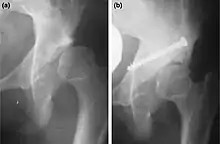

Two main types of osteotomies are used in the correction of hip dysplasias and deformities to improve alignment/interaction of acetabulum – (socket) – and femoral head (femur head) – (ball), innominate osteotomies and femoral osteotomies. The bones are cut, reshaped or partially removed to realign the load-bearing surfaces of the joint.[3]

_open_reduction%252C_capsulorrhaphy_and_Dega_and_(b)_Chiari_surgery.jpg.webp)

b. Same hip after addition of Chiari medial displacementosteotomy.[4]

Adjustments are made to part of the hip-bone. Many operating methods and variations have been developed. They are defined by the type of cut and adjustment made. Some acetabular procedures are named after the surgeons who first described them as Salter (R. Salter), Dega (W. Dega), Sutherland (D.H. Sutherland), Chiari (K. Chiari): other names one may encounter are Ludlov, P. Pemberton, and James B. Steele. Some are named after the shape of cut (e.g. Chevron, Wedge) or the way the bones are aligned (Dial=old style rotary dial phone).